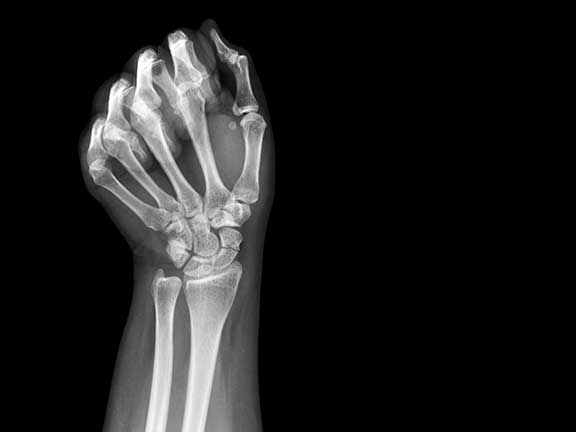

Stres kırığı, aslında tam olarak bir kırık değildir. Ayağın yük taşıması sırasında her bölgenin farklı işlevleri vardır. Yürüyüş esnasında ayağın her bölgesi belli miktarda yük taşır. Ancak ayağın anatomik yapısı zorlanırsa ve yanlış yerlere fazla miktarda yük bindirilirse kemiğin basınç altında kalmasına sebep olunur. Basınç ise tarak ve kaval kemiklerinde ödeme neden olur. Ödem geliştikçe kemiğin içerisindeki basıncı arttırır. Bu basınç ise hastaya ağrı olarak yansır.

Stres kırığı daha çok alt baldır kemikleri ve ayak tarak kemiklerinde meydana gelir. Bunun sonucunda ise küçük çatlaklar meydana gelir. Araştırmalar sonucu stres kırığının daha çok enerji gerektiren sporları yapan kişilerde oluştuğu görülmüştür. Bu enerji gerektiren sporlar ise basketbol, tenis, atletizm gibi sporlardır. Çünkü bu sporlarda zemine ayak çarpma hareketi daha çok yapılır. Stres kırığı ayrıca saha ve pist sporları ile uğraşanlarda da görülebilir.